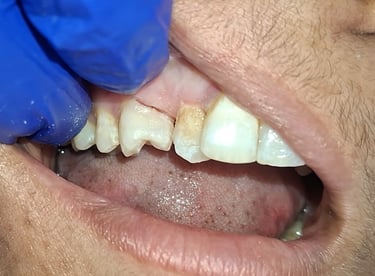

Before

After

All images shown here are real tooth colored filling cases treated at our clinic with patient consent.

At Shree Dental Care, cosmetic fillings are placed carefully with a focus on comfort, precision and long-term durability. We ensure minimal tooth cutting and natural-looking results.

If you are looking for aesthetic tooth colored filling in Shyamal, Ahmedabad, you can book an appointment with our clinic.